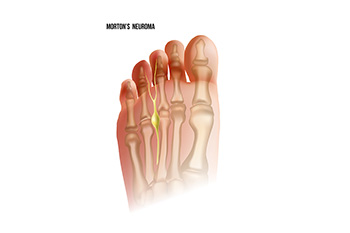

Facts About Morton's Neuroma

Morton's neuroma is a painful condition affecting the ball of the foot, most commonly between the third and fourth toes. It involves the thickening of tissue surrounding one of the nerves leading to the toes, causing sharp, burning pain or a feeling of something being stuck inside the ball of the foot. Contributing factors include wearing high heels or tight shoes, which put pressure on the toes and the nerves. Symptoms can also include numbness or a tingling sensation in the toes. Relief methods include wearing wider shoes with lower heels, using arch supports or foot pads, and resting the feet to reduce pressure. In more severe cases, medical treatments such as corticosteroid injections or surgery may be necessary. If pain has developed in this part of your foot, it is suggested that you visit a podiatrist who can provide a proper diagnosis and treatment.

Morton’s neuroma is a very uncomfortable condition to live with. If you think you have Morton’s neuroma, contact Deborah Rosenfeld of Rosenfeld Podiatry. Our doctor will attend to all of your foot care needs and answer any of your related questions.

Morton’s Neuroma

Morton's neuroma is a painful foot condition that commonly affects the areas between the second and third or third and fourth toe, although other areas of the foot are also susceptible. Morton’s neuroma is caused by an inflamed nerve in the foot that is being squeezed and aggravated by surrounding bones.

What Increases the Chances of Having Morton’s Neuroma?

- Ill-fitting high heels or shoes that add pressure to the toe or foot

- Jogging, running or any sport that involves constant impact to the foot

- Flat feet, bunions, and any other foot deformities

Morton’s neuroma is a very treatable condition. Orthotics and shoe inserts can often be used to alleviate the pain on the forefront of the feet. In more severe cases, corticosteroids can also be prescribed. In order to figure out the best treatment for your neuroma, it’s recommended to seek the care of a podiatrist who can diagnose your condition and provide different treatment options.

Morton's Neuroma

A neuroma is a thickening of nerve tissue and can develop throughout the body. In the foot, the most common neuroma is a Morton’s neuroma; this typically forms between the third and fourth toes. The thickening of the nerve is typically caused by compression and irritation of the nerve; this thickening can in turn cause enlargement and, in some cases, nerve damage.

Neuromas can be caused by anything that causes compression or irritation of the nerve. A common cause is wearing shoes with tapered toe boxes or high heels that force the toes into the toe boxes. Physical activities that involve repeated pressure to the foot, such as running or basketball, can also create neuromas. Those with foot deformities, such as bunions, hammertoes, or flatfeet, are more likely to develop the condition.

Symptoms of Morton’s neuroma include tingling, burning, numbness, pain, and the feeling that either something is inside the ball of the foot or that something in one’s shoe or sock is bunched up. Symptoms typically begin gradually and can even go away temporarily by removing one’s shoes or massaging the foot. An increase in the intensity of symptoms correlates with the increasing growth of the neuroma.

Treatment for Morton’s neuroma can vary between patients and the severity of the condition. For mild to moderate cases, padding, icing, orthotics, activity modifications, shoe modifications, medications, and injection therapy may be suggested or prescribed. Patients who have not responded successfully to less invasive treatments may require surgery to properly treat their condition. The severity of your condition will determine the procedure performed and the length of recovery afterwards.